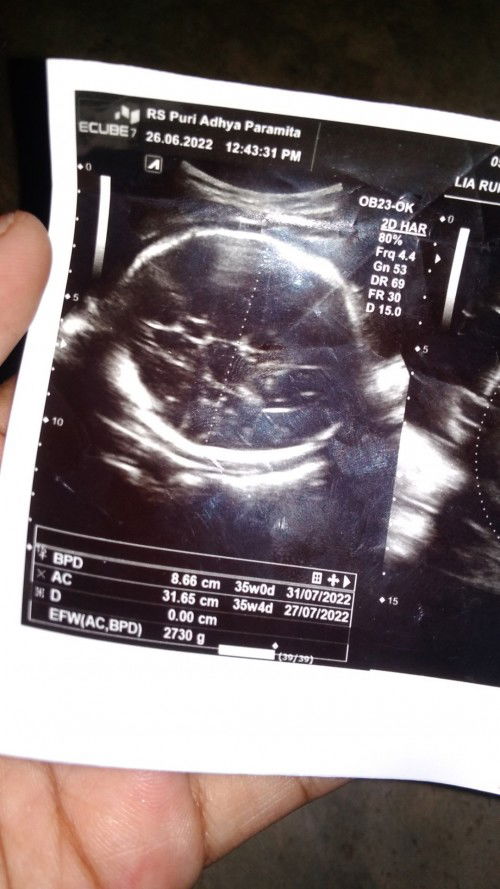

Seputar Foto USG

Bund, ini maksudnya gimana ya Maaf baru pertama hamil jadi masih bingung untuk baca dan itungannya #seriusnanya #bantusharing #ingintahu

Itu kehamilan bunda udah 35Minggu4hari . berat badan nya 2,7kg . emang ga di jelasin ya bun sama dokter nya. itu USG pertama bukan bunda